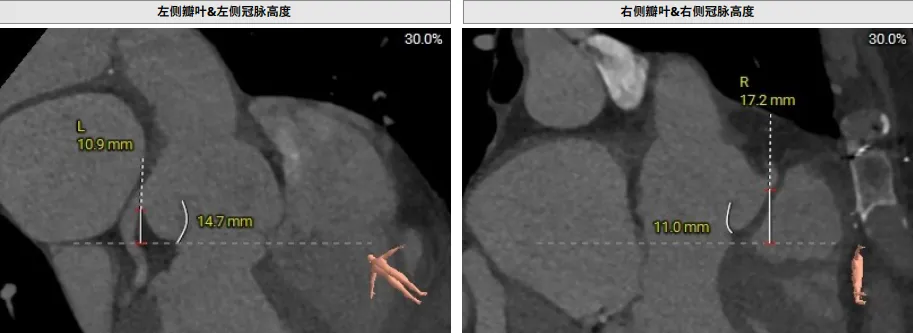

患者为主动脉瓣三叶瓣,瓣叶增厚,瓣叶未见明显钙化,存在三个瓣窦,窦部增大,分布较均匀;主动脉瓣环周长折算直径29.4mm;双侧冠脉开口高度可LCA:10.9mm,RCA:17.2mm;双侧冠脉未见明显钙化;最佳投射角度:右窦中心体位:CRA:16°/LAO:13°(其它参考角度如下图); 模拟切口位置:第6-7肋间;模拟输送器角度为143°;室间隔基底部稍增厚;升主动脉人工血管置换术后。